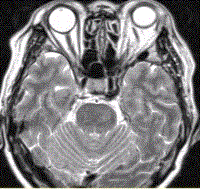

问题 女性,62岁。外伤后左侧突眼。MRI显示如下图。 需与该病鉴别诊断的疾病包括

选项 A.Tolosa-Hunt综合征 B.海绵窦神经鞘瘤 C.海绵窦脑膜瘤 D.海绵窦动脉瘤 E.海绵窦AVM F.海绵窦海绵状血管瘤

答案 ABCD